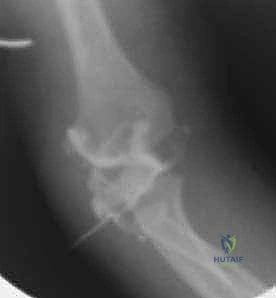

التصوير بالأشعة السينية (X-rays)

الأشعة السينية هي الأداة الأساسية للتشخيص. يتم أخذ صور في وضعيات متعددة (أمامية خلفية AP، وجانبية Lateral، وربما مائلة Oblique).

لماذا الكسر مخادع؟ في الأطفال الصغار، تكون أجزاء كبيرة من مفصل الكوع عبارة عن غضاريف لم تتحول إلى عظم صلب بعد (لم تتعظم). الأشعة السينية لا تظهر الغضاريف، بل تظهر العظام فقط. لذلك، قد يبدو الكسر في الأشعة صغيراً جداً (مجرد قشرة عظمية صغيرة مكسورة)، بينما في الواقع، هناك كتلة غضروفية كبيرة جداً (تحتوي على سطح المفصل وصفيحة النمو) قد انفصلت تماماً وتدور حول نفسها.

هنا تتجلى خبرة الجراح. الطبيب غير المتخصص قد يرى الأشعة ويقول للآباء "إنه كسر بسيط يحتاج لجبس"، بينما الخبير مثل أ.د. محمد هطيف يدرك من خلال النظرية التشريحية وخبرته الطويلة أن هذا الكسر غير مستقر ويحتاج لتدخل جراحي.